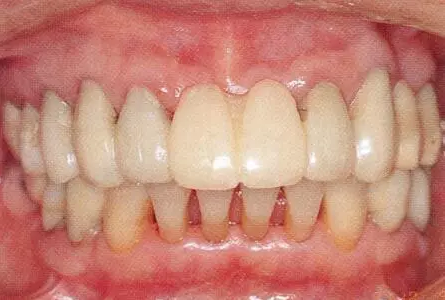

33333.png

▲圖19-13

佩戴最終修復(fù)體時(shí)的正面照片。